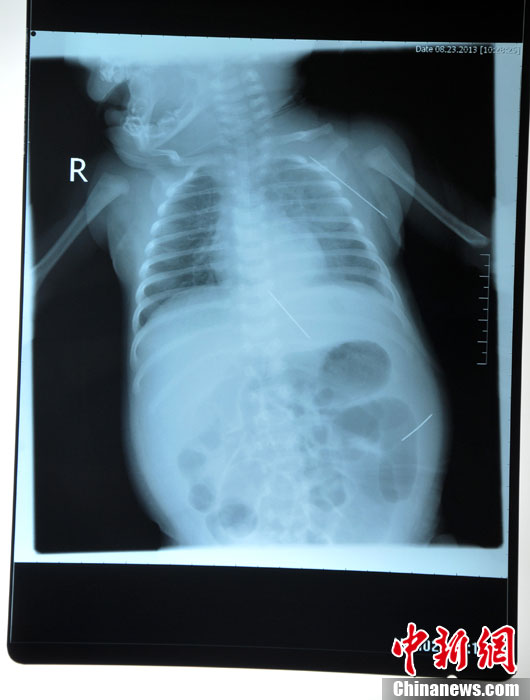

8月23日,黑龍江被“縫衣針”扎傷女?huà)朐诠枮I醫(yī)科大學(xué)附屬第一醫(yī)院進(jìn)行手術(shù),成功取出三根長(zhǎng)達(dá)4.5厘米的縫衣針,目前患兒正在術(shù)后觀察中,尚未脫離危險(xiǎn)期。圖為三根鋼針在嬰兒體內(nèi)的各個(gè)位置。(哈爾濱醫(yī)大一院供圖)中新社發(fā)